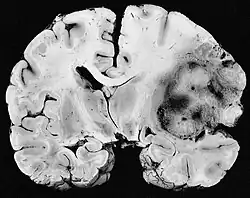

Um sarcoma é um cancro (câncer)/neoplasia que atinge células da mesoderme, em contraste com os cânceres mais comuns, que atingem a parte mais superficial ou interna do tecido. Pode atingir osso, cartilagem, gordura, músculo, vasos sanguíneos, ou tecidos moles. O termo advém do termo grego e significa "crescimento carnoso". São os tipos de câncer que mais fazem metástase e portanto os mais perigosos e difíceis de serem tratados. [1]

Sarcomas de baixa gravidade são geralmente tratados cirurgicamente, sem necessariamente precisar de radioterapia ou a quimioterapia, mas elas possam ser usadas dependendo do caso. Sarcomas de grau intermediário e grau alto são mais frequentemente tratados com uma combinação de cirurgia, quimioterapia e radioterapia, pois tumores de grau mais elevado são mais propensos a sofrer metástase, então precisam ser tratados de forma mais agressiva.[3] O reconhecimento de que muitos sarcomas são sensíveis à quimioterapia melhorou drasticamente a sobrevida dos pacientes. Por exemplo, na era antes da quimioterapia, a sobrevivência a longo prazo para pacientes com osteossarcoma localizado era apenas aproximadamente 20%, mas agora subiu para 60-70%.[4]